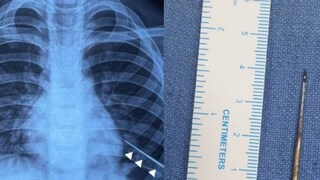

കടുത്ത പനിയും രക്തം ചുമച്ച് ഛർദ്ദിക്കുകയും ചെയ്തതിനെ തുടർന്ന് കുട്ടിയെ ആദ്യം സ്വകാര്യ ആശുപത്രിയിൽ പ്രവേശിപ്പിക്കുകയായിരുന്നു. ഇവിടെ നിന്നാണ് എയിംസിലേക്ക് മാറ്റുന്നത്. എക്സ് റേയിൽ ഇടത് ശ്വാസകോശത്തിൽ സൂചി കണ്ടെത്തി. ശ്വാസകോശത്തിൽ ആഴ്ന്നിറങ്ങിയ നിലയിലായിരുന്നു സൂചിയുണ്ടായിരുന്നത്. ശസ്ത്രക്രിയ ഉപകരണങ്ങൾ ഉപയോഗിച്ച് പുറത്തെടുക്കാൻ സാധിക്കാത്തതിനെ തുടർന്നാണ് കാന്തം ഉപയോഗിച്ചതെന്ന് ഡോക്ടർമാർ പറയുന്നു.

ഇതിനായി ഡൽഹിയിലെ ചാന്ദ്നി ചൗക്കിൽ നിന്ന് 4 mm വീതിയും 1.5 mm കനവുമുള്ള കാന്തം വാങ്ങുകയായിരുന്നു. ഈ കാന്തം ലഭ്യമല്ലായിരുന്നുവെങ്കിലോ, ശ്വാസകോശത്തിൽ സൂചി ദൃശ്യമല്ലായിരുന്നുവെങ്കിലോ കുട്ടിക്ക് തുറന്ന ഹൃദയ ശസ്ത്രക്രിയ നടത്തേണ്ടി വരുമായിരുന്നുവെന്ന് പീഡിയാട്രിക് വിഭാഗത്തിലെ അഡീഷണൽ പ്രൊഫസർ ഡോ. വിശേഷ് ജെയിൻ പറഞ്ഞു.

ശസ്ത്രക്രിയയ്ക്കു ശേഷം കുട്ടി ഡിസ്ചാർജ് ചെയ്ത് മടങ്ങിയതായും ഡോക്ടർ അറിയിച്ചു. ശ്വാസകോശത്തിനുള്ളിൽ വളരെ ആഴത്തിലായിരുന്നു സൂചിയുണ്ടായിരുന്നത്. അതിനാൽ പരമ്പരാഗത ശസ്ത്രക്രിയാ രീതികൾ ഫലപ്രദമല്ലെന്ന് കണ്ടാണ് കാന്തം ഉപയോഗിച്ചതെന്ന് ഡോക്ടർ വിശദീകരിച്ചു. കാന്തം ശ്വാസനാളത്തിലേക്ക് പോകാതെ, സൂചിയുടെ സ്ഥാനത്തേക്ക് എത്തിക്കുക എന്നതായിരുന്നു പ്രധാന വെല്ലുവിളി. നൂലം റബ്ബർ ബാൻഡും ഉപയോഗിച്ച് കാന്തം ഭദ്രമായി ഘടിപ്പിച്ച് പ്രത്യേക ഉപകരണമാണ് ഡോക്ടർമാർ ഇതിനായി കണ്ടെത്തിയത്.

ഇടതു ശ്വാസകോശത്തിനുള്ളിൽ സൂചിയുടെ കൃത്യമായ സ്ഥാനം കണ്ടെത്താൻ എൻഡോസ്കോപി നടത്തി. സൂചിയുടെ അഗ്രഭാഗം മാത്രമേ ഇതുവഴി കാണാൻ സാധിക്കുകയുള്ളൂ. ഇതിനു ശേഷം കാന്തം ഘടിപ്പിച്ച ഉപകരം സൂക്ഷ്മതയോടെ സ്ഥാനത്തേക്ക് കയറ്റി. കാന്തത്തോട് സൂചി പെട്ടെന്ന് അടുക്കുകയും വളരെ വേഗത്തിൽ പുറത്തെടുക്കാൻ സാധിച്ചുവെന്നും ഡോക്ടർ പറഞ്ഞു.